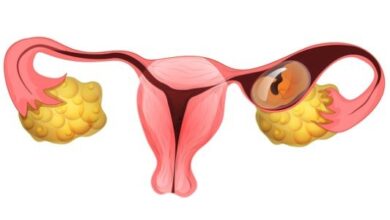

- توسّع عنق الرحم (بالإنجليزية: Cervical dilation or effacement) والذي يبدأ قبل عدّة أسابيع من الولادة ويقوم الطبيب بقياسه في كل زيارة في الشهر الأخير من الحمل.[٤]

- خروج سائل مخاطيّ ذات لون بنيّ مصحوب ببعض الدم، وهو ما يُعرَف بسدادة عنق الرحم المخاطيّة (بالإنجليزية: Cervical mucus plug)، وهو عبارة عن سائل مخاطيّ يعمل على إغلاق فتحة عنق الرحم خلال الحمل، وبعد خروج هذه السدادة قد يبدأ الطلق مباشرة أو خلال عدّة أيّام.[٢]